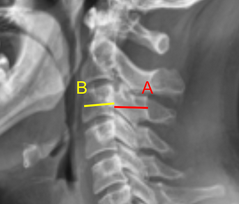

Image Type Cervical Spine X-Ray CT Scan MRI Scan Atlantodental Interval (ADI) Basion-Axial Interval Basion-Dens Interval (BDI) C2 Tilt C2–C7 Coronal Cobb Angle Cervical C2-7 lordosis C2-C7 Translation Chamberlain’s Line / McGregor’s Line Flexion-Extension George’s Line (Posterior Cervical Line) K-Line Interpedicular Distance (IPD) Occiput-C2 Angle Occipital Condyle–C1 Interval (CCI) Posterior Atlantodental Interval (PADI) Power’s ratio Sagittal Canal Diameter Sagittal Vertical Axis (SVA) Spinolaminar line Swischuk Line T1 Slope Torg/Pavlov Canal-to-Body Ratio